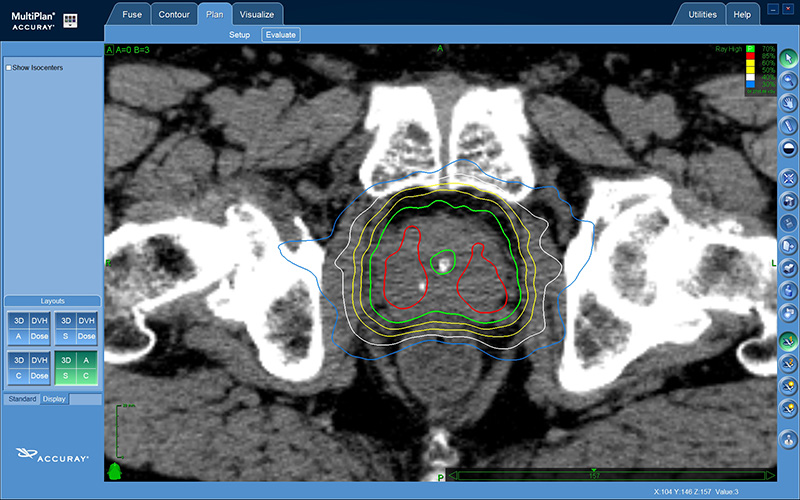

Die Cyberknife-Radiochirurgie ist eine sehr sichere Methode, bei der eine hohe Dosis den Tumor äußerst präzise erreicht. Der starke Dosisabfall um den Tumor schont sie umliegendes Gewebe wie Blase, Rektum und Nerven bestmöglich. Die Prostata bleibt bei dieser Therapie erhalten.

Das Planungsbeispiel zeigt die starke Dosiskonzentration auf die Prostata mit minimaler Umgebungsbelastung. Dies ist möglich, weil der Roboter sich mit der Prostatabewegung während der Behandlung mitbewegt.